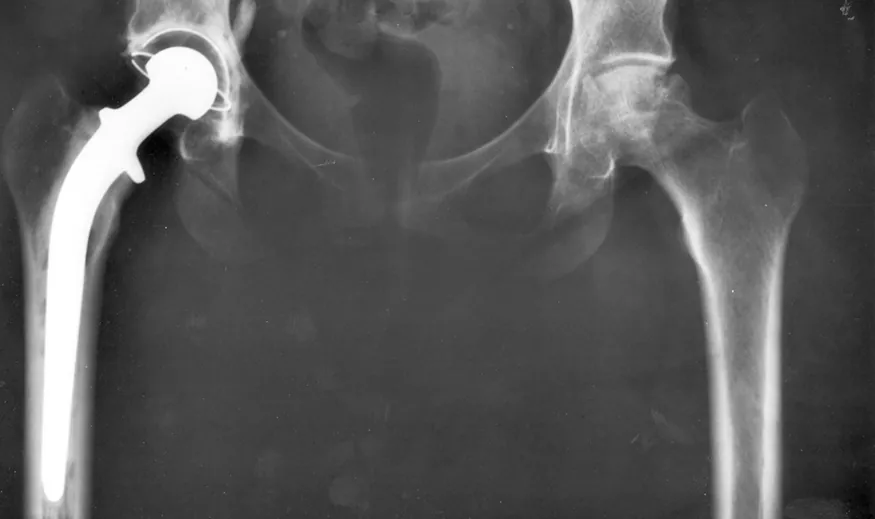

An x-ray image of a person’s hips. The right hip joint (on the left in the photograph) has been replaced. A metal prosthesis is cemented in the top of the right femur and the head of the femur has been replaced by the rounded head of the prosthesis. A white plastic cup is cemented into the acetabulum to complete the two surfaces of the artificial ball and socket joint.

Figure 5.1 Total hip replacement surgery has become a common procedure. The head (or ball) of the patient’s femur fits into a cup that has a hard plastic-like inner lining. (credit: National Institutes of Health, via Wikimedia Commons)

Describe the forces on the hip joint. What means are taken to ensure that this will be a good movable joint? From the photograph (for an adult) in Figure 5.1, estimate the dimensions of the artificial device.